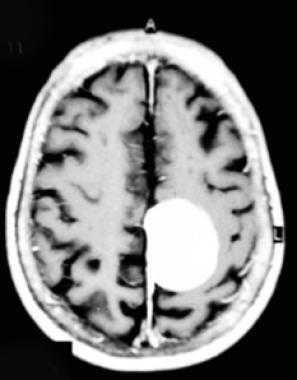

Перед вами - два снимка, сделанных в одном режиме. Снимок снизу - норма. Какое заболевание, в таком случае, есть на верхнем снимке? Чтобы понять это, нужно сравнить эти изображения. Явно видно отличие - на верхнем снимке в правой части головного мозга есть новообразование. Разница еще заметнее, если сравнить левую и правую части того же снимка.

Отметим его красной окружностью. Визуально оно представляет собой узел, неоднородный по окраске и отличающийся от серого и белого вещества головного мозга. В таких случаях, чтобы точно определить границы опухоли и определить её тип исследование повторяют с контрастом. Введение контрастного препарата в кровь через локтевую вену приводит к накоплению контрастного вещества в тканях опухоли - нормальные здоровые ткани его практически не накапливают. И мы получаем следующую картину, показанную на рисунке справа. Яркая окраска опухоли соответствует накопленному контрасту - теперь можно не только сказать, где опухоль, но и примерно определить, что это доброкачественная опухоль, так как она имеет четкие границы (злокачественные опухоли прорастают окружающие ткани, из-за чего границы будут размытыми и не такими четкими).